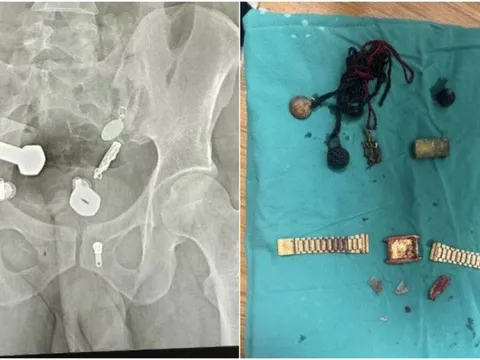

Người đàn ông Ấn Độ nhập viện vì đau dạ dày dữ dội khiến không thể ăn uống, song kết quả chụp X-quang khiến bác sĩ sững sờ khi phát hiện hàng loạt dị vật, trong đó có cả một chiếc đồng hồ.